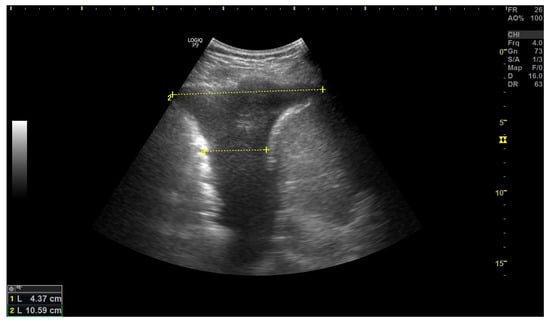

3.3. Pleural Effusion

- Yamanoğlu, A.; Çelebi Yamanoğlu, N.G.; Parlak, İ.; Pınar, P.; Tosun, A.; Erkuran, B.; Akgür, A.; Satılmış Siliv, N. The Role of Inferior Vena Cava Diameter in the Differential Diagnosis of Dyspneic Patients; Best Sonographic Measurement Method? Am. J. Emerg. Med. 2015, 33, 396–401. [Google Scholar] [CrossRef] [PubMed]

- Blehar, D.J.; Dickman, E.; Gaspari, R. Identification of Congestive Heart Failure via Respiratory Variation of Inferior Vena Cava Diameter. Am. J. Emerg. Med. 2009, 27, 71–75. [Google Scholar] [CrossRef]

- Kajimoto, K.; Madeen, K.; Nakayama, T.; Tsudo, H.; Kuroda, T.; Abe, T. Rapid Evaluation by Lung-Cardiac-Inferior Vena Cava (LCI) Integrated Ultrasound for Differentiating Heart Failure from Pulmonary Disease as the Cause of Acute Dyspnea in the Emergency Setting. Cardiovasc. Ultrasound 2012, 10, 49. [Google Scholar] [CrossRef]

- Hassan, M.; Rizk, R.; Essam, H.; Abouelnour, A. Validation of Equations for Pleural Effusion Volume Estimation by Ultrasonography. J. Ultrasound 2017, 20, 267–271. [Google Scholar] [CrossRef]

- Laursen, C.B.; Clive, A.; Hallifax, R.; Pietersen, P.I.; Asciak, R.; Davidsen, J.R.; Bhatnagar, R.; Bedawi, E.O.; Jacobsen, N.; Coleman, C.; et al. European Respiratory Society Statement on Thoracic Ultrasound. Eur. Respir. J. 2021, 57. [Google Scholar] [CrossRef]

- Grimberg, A.; Shigueoka, D.C.; Atallah, A.N.; Ajzen, S.; Iared, W. Diagnostic Accuracy of Sonography for Pleural Effusion: Systematic Review. Sao Paulo Med. J. 2010, 128, 90–95. [Google Scholar] [CrossRef] [PubMed]